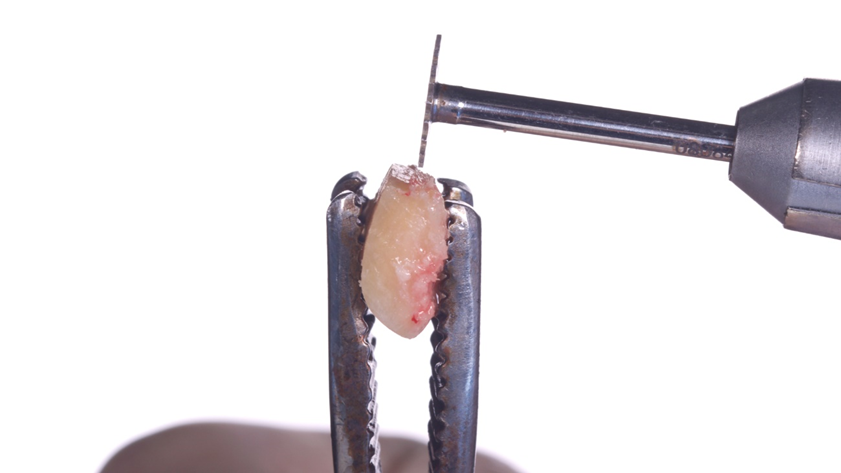

Homem de 60 anos foi encaminhado para reabilitação implantossuportada na região molar inferior direita (Figura 1). O volume ósseo remanescente tridimensional foi acessado por meio de tomografia computadorizada. Revelou uma deficiência vertical de modo que um aumento vertical foi planejado antes da colocação do implante. Seu histórico médico foi verificado e não foram encontradas comorbidades nem condições alérgicas. Não houve achados clínicos intraorais anormais, mas uma deficiência vertical na área molar inferior direita. Nenhum achado anormal foi perceptível no exame extraoral. Um enxerto autógeno em bloco ósseo dividido foi planejado para aumento horizontal e o ramo ipsilateral foi o local doador de escolha. A cirurgia foi realizada sob anestesia local com Articaína 4% e adrenalina 1:100.000. O paciente foi prescrito para enxaguar com Clorexidina 0,12% no pré-operatório, bem como tomar 1mg de Amoxicilina e 8mg de Dexametasona P.O. uma hora antes da cirurgia. Uma incisão mucoperiosteal foi realizada com bisturi número 15C desde o ramo mandibular até a borda mesiovestibular do primeiro pré-molar juntamente com uma incisão perpendicular obliquamente no vestíbulo mandibular. Após o descolamento da mucosa vestibular e liberação do nervo mentoniano, a mucosa lingual também foi descolada (Figura 2). Duas osteotomias verticais e uma horizontal foram realizadas no ramo mandibular com broca 701 para retirada do bloco ósseo necessário à reconstrução horizontal (Figura 3). Após a retirada do enxerto com auxílio de um elevador radicular, o bloco foi cortado longitudinalmente em dois pedaços finos com brocas discais e o osso esponjoso foi raspado para que pudesse ser utilizado como osso lascado (Figuras 4 a 8). Os blocos foram fixados na área edêntula. Um bloco foi fixado na face vestibular e o outro na face lingual. Cada um deles foi fixado com dois parafusos de osteossíntese de 1,5 mm e o osso lascado foi inserido no espaço entre eles (Figuras 9 e 10). A ferida foi fechada com fio de polipropileno 5-0, que foi retirado após 15 dias (Figura 11). A cirurgia cicatrizou sem intercorrências e o paciente recebeu prescrição de amoxicilina 500 mg P.O. a cada oito horas durante sete dias e ibuprofeno 600 mg a cada seis horas durante cinco dias.